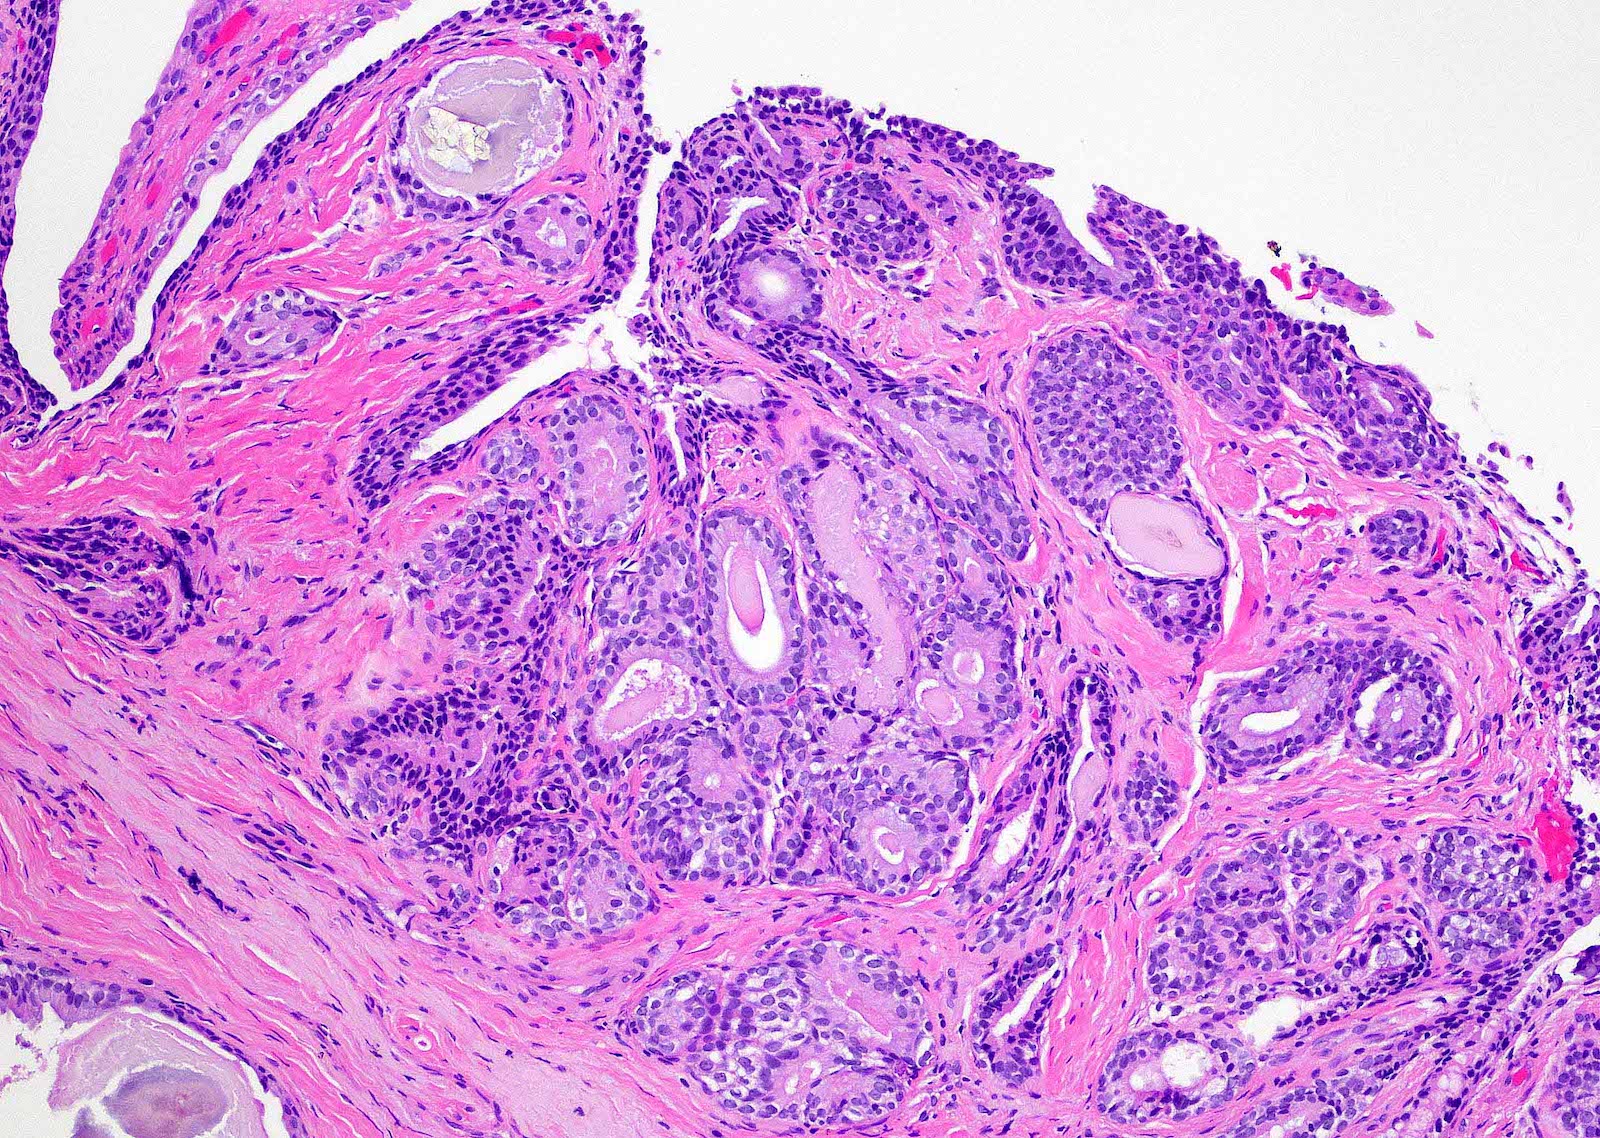

Microscopic (histologic) images

Contributed by Y. Albert Yeh, M.D., Ph.D.

Fibroepithelial polyp

- Fibroepithelial urethral polyp (Am J Surg Pathol 2005;29:460):

- Pattern 1: most common pattern includes the following features

- Broad cloverleaf-like and club-like projections covered by normal urothelium and composed of dense fibrovascular stroma with florid cytitis cystica et glandularis (most common morphologic variant)

- Back to back glands present in the stalk

- Anastomosing nests of benign urothelial cells resembling inverted papilloma

- Dilated cysts with intracystic papillary contents

- Degenerative reactive atypia of stromal cells

- Pattern 2: numerous small papillae with dense fibrous cores and areas of glandular differentiation

- Pattern 3: urothelial lined broad edematous papillae mimicking polypoid urethritis; urothelial lined broad fibrous papillae with subepithelial edema

- Pattern 1: most common pattern includes the following features

A 50 year old man presented with dysuria and hematuria for 3 months. Cystoscopic examination showed a polypoid mass protruded from the posterior wall of the prostatic urethra. Cystoscopic excision of the polyp and histopathological examination were performed. The microphotograph of the urethral polyp is shown above. What is the diagnosis?